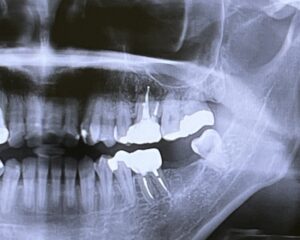

外傷歯とは 歯そのものや顔面、口唇などを激しくぶつけて傷害を負った歯のことを「外傷歯」と言います。交通事故が代表的な例ですが、転倒やラグビー、柔道などのスポーツが原因で起こることもあります。外からの衝撃で、主に前歯が外傷歯になることが多く見られます。患者の多くは子どもですが、大人にも起こるため注意が必要です。

外傷歯の程度 外傷歯は以下の程度に分けられます。ただし、「唇を切った」「顔面裂傷」などの軟組織の傷害はここでは除外しています。

• 見た目は何ともない:見た目は何ともなくても、打撲によって歯の神経が死んだり、歯の根が吸収されたりすることがあります。

• 歯にヒビが入った:エナメル質に軽くヒビが入った程度なら痛みはありませんが、象牙質に達すると少ししみることがあります。

• 歯が欠けた(折れた):エナメル質の部位が欠けた場合は軽度、象牙質の部位が欠けた場合は中程度ですが、歯髄(神経)の部位で欠けた場合は重度です。さらに歯の根の部分で折れた場合はより深刻です。

• 歯がグラグラ動く・抜けた:歯が折れずにグラグラ動いたり、転位したり、完全に抜けてしまうことがあります。これを歯牙脱臼と言います。歯の動揺・転位により、接触痛などの痛みを伴うことが多いです。

• 歯槽骨または顔面骨の骨折:衝撃が周囲の骨にまで影響し、ひどいときは顎の骨が折れることもあります。状況によっては口腔外科の受診をおすすめします。